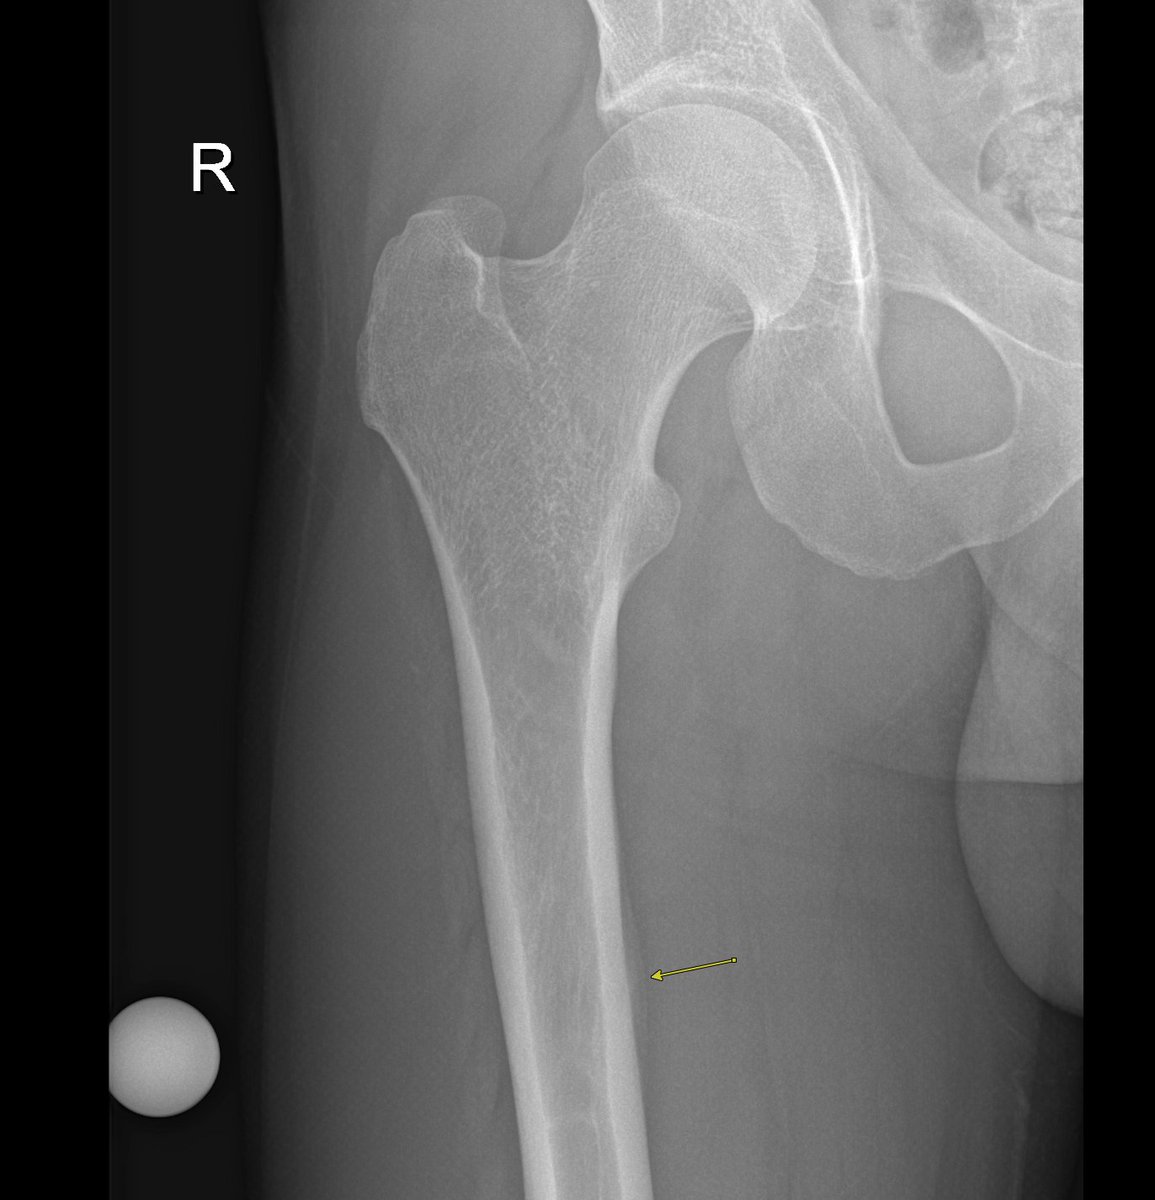

Radiograph at time of diagnosis. Periosteal and endosteal thickening Endosteal And Periosteal Edema It’s typically the response to an injury or a condition like osteoarthritis. the continuum of findings ranges from periosteal edema (grade i), to both periosteal edema and marrow edema seen on. bone marrow edema is a buildup of fluid in the bone marrow. In rheumatoid arthritis edema may precede an erosion. thin mineralized periosteum may be difficult. Endosteal And Periosteal Edema.